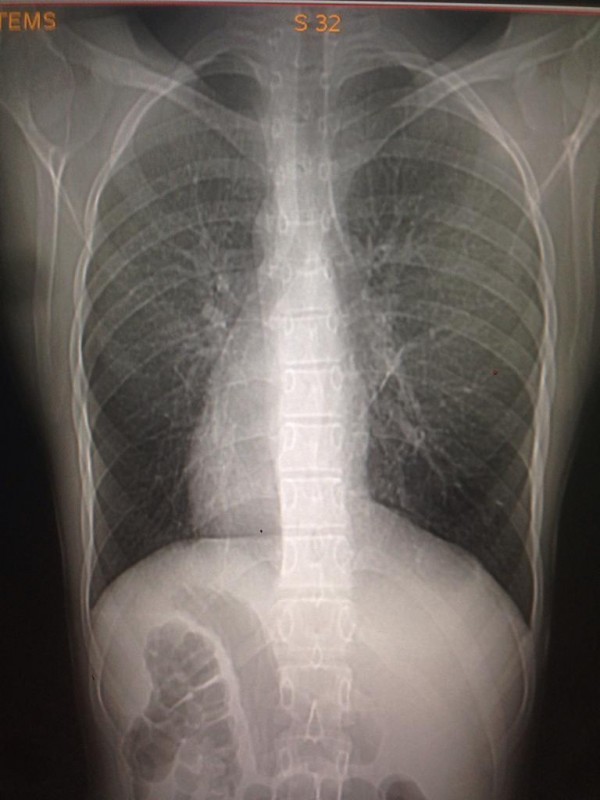

Транспозиция внутренних органов - редкий вариант биологически нормальной анатомии, в котором основные внутренние органы имеют зеркальное расположение по сравнению с обычным нормальным положением: сердце - справа, печень - слева, желудок - справа. Такой случай встречается у одного человека из 10 тысяч. Главная причина - мутация генов, и передается аномалия по наследству.

Транспозиция внутренних органов. Снимок предоставлен Сундетом Саргеловым

К сожалению, точных статистических данных обо всех казахстанцах, сердце которых расположено с правой стороны грудной клетки, нет. Однако, по словам медработника, в нашей стране ситуация аналогична мировой. Таким образом, если население Казахстана в среднем составляет 18 миллионов, то по вычету получается, что среди нас живет около 1800 правосердечников. В основном люди узнают об аномалии, когда делают рентген. К тому же зачастую посмертное вскрытие не проводят, так как родные умершего бывают против этой процедуры.